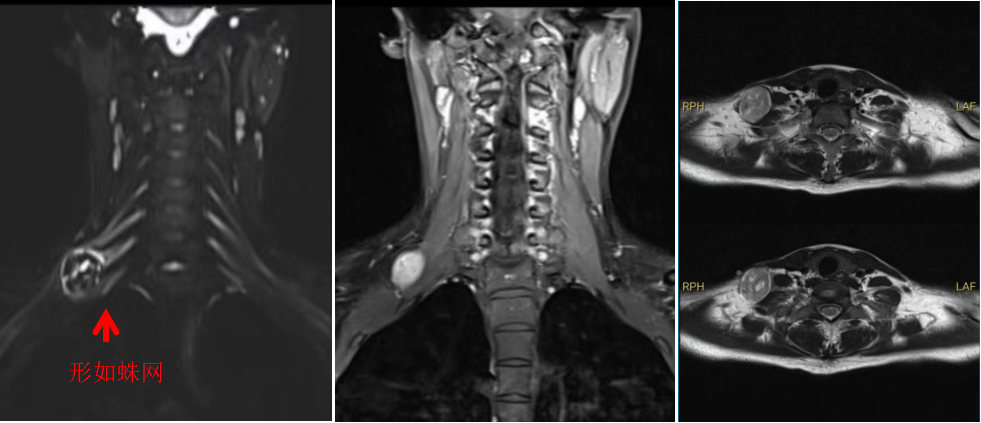

图1

手术由林飞跃医生主刀,团队医生相互配合。由于王女士的肿瘤生长于颈部重要神经丛之中,就宛如盘踞在“蜘蛛网”上(图1),给手术带来了巨大的挑战。医生们如同在一片错综复杂的神经网络中寻找出路,每一步操作都需要格外谨慎,生怕触碰到任何一根关键的神经纤维。林医生一点点地将肿瘤与周围的神经组织分离,经过近两个小时的紧张手术,将肿瘤完整切除。术后,王女士上肢功能恢复完好。